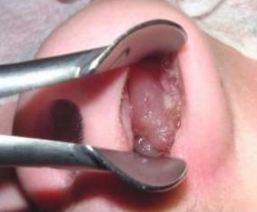

3. boca

1. inspeccion

1. Labios: aspecto y simetria

1. Dentadura: presencia de todas las piezas dentales, si hay caries o protesis

1. Mucosa bucal: lesiones, color y humedad

1. Encías: aspecto, coloración, aseo, acumulación de sarro en el cuello de los dientes

1. Lengua: aspecto (ej. lengua geográfica), con surcos profundos (ej. lengua fisurada), color, sensibilidad, seborrea,

1. paladar y piso de la lengua: aspecto, fisuras

1. palpacion

1. base de la lengua, amigdalas ,encias